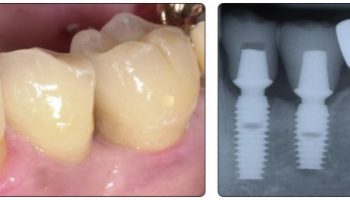

Las plataformas que tiene el implante Bicon, mucho más anchas que las espiras de cualquier implante atornillado, le proporcionan una estabilidad única permitiendo realizar casos con relaciones implanto prótesis de más de 1:4 con total garantía.

El hueso que se forma entre las plataformas, no es un hueso aposicional como el que se forma alrededor de las espiras de los implantes atornillados, sino que es un hueso haversiano, de tipo cortical, muchísimo más resistente a las fuerzas laterales que el hueso aposicional que soportan los implantes atornillados.

En implantes cortos tenemos más palanca de la parte protésica sobre la conexión, la conexión Bicon (sellado en frío, pieza única) elimina este problema comportándose exactamente igual que un implante largo.